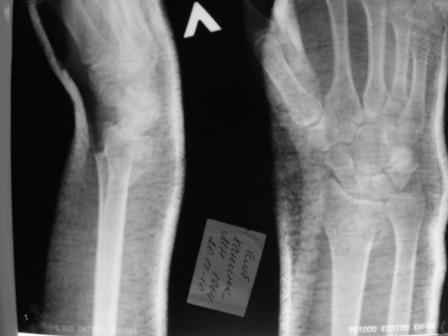

Уважаемые коллеги.Прошу обсудить случай лечения перелома дистального метаэпифиза лучевой кости. Ситуация скандальная и крайне неблагоприятная. Больная с патологической обстоятельностью мышления, склонностью к сутяжничеству, патологическими умозаключениями, не поддающимися коррекции (см. психиатрию, правда офиц. диагноза нет). В данном случае есть ряд ошибок с нашей стороны, прежде всего в отношении качества ведения документации (за что получил административное взыскание, по делом мне дураку). В остальном- придерживались в лечении подхода классический советской школы. Так как умную операцию…… сами знаете… 15.12- перелом луча в Москве. Там же репозиция, гипс. Дальнейшее лечение у нас в ЦРБ. 20.12.- вторичное смещение в гипсе21.12- под внутривенным наркозом- репозиция, гипсовая лонгета. Дальше начинается самое интересное. После репозиции больная заявила, что я (репозицию делал я) порвал ей все связки в суставе, посинел у нее 5 палец, якобы я за него тянул и т. д. На самом деле на 2 сутки после репозиции рука немного отекла и было незначительное сдавление гипсом, который был ослаблен. Дальнейшее лечение консервативное. Через 6 недель- гипс снят, назначено ЛФК. Пациентка крайне недовольна. Говорит, что на снимке у нее выступает кость, я ей сломал руку и.т.д. В общем началось. Пациентка прочитала в интернете наверное все, что есть по данной травме.По заключениями рентгенологов и консультанта из КДЦ областной больницы - стояние отломков допустимое. Объективно говоря- снижена высота лучевой кости, диастаз лучелоктевого сочленения, и не сросся шиловидный отросток. однако на РКТ при сравнении с другой стороной- разница незначительная. Дальше в одной из больниц нашей области и одной из больниц Москвы (вроде бы КГБ 53) врачи сказали, что репозиция сделана плохо. Нужна операция (восстановить длину лучевой кости), даже один из них предложил РЕДРЕССАЦИЮ (хи-хи) с наложением аппарата Илизарова. Что это для данной больной- радость неописанная. (см. описание психического статуса). Ничем другим, кроме зарабатывания дешевого авторитета объяснить данный факт не могу.Кстати, у больной еще нейропатия локтевого нерва.Для разрешения конфликта больная направлена на консультацию в ЦИТО на 03.03.11.

1. Репозиция от 21.12.10 была выполнена лучше, чем первичная.

Заключение: Консолидированный в неправильном положении перелом дистального метафиза левой лучевой кости. Ротационная контрактура левого предплечья. Рекомендовано- разработка, консультация через 2 месяца.

Объективно: пронация почти полная, супинация ограничена, ладонная флексия около 20, тыльная 10. Гипостезия в зоне инервации локтевого нерва. Незначительный отек. Хват кисти полный. Сила 4 балла.

В общем, типичная картина раннего восстановительного периода после снятия гипса. Визуально конечность не изменена.